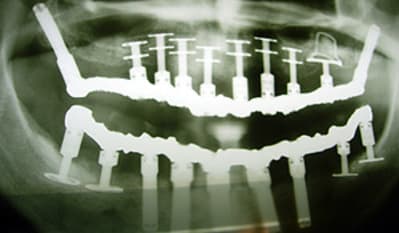

c'est du juxta osseux ca?

pas du juxta osseux ,ignare, des implants à plaque!

j'aimerais qu'on m'explique ce qu'on voit sur la pano précisément,

c'et spas ironique, c'ets juste pour savoir un truc.

Merci beaucoup.

> j'aimerais qu'on m'explique ce qu'on voit sur la pano précisément,

> c'et spas ironique, c'ets juste pour savoir un truc.

> Merci beaucoup.

bon, j't'explique

en haut c'est ula-up barbimplant

(et barbosdur et barbicrête et barbalatérale et barbalalaaaaa)

L'oeil averti remarquera la présence d'un type d'implant particulier, les implants à plaque. Ces implants permettent d'équiper des patients qui ne pouvaient pas être traités jusqu'à ce jour. Ces implants ne sont pas encore recouverts d'os, les radiographies ayant été prises juste après la chirurgie implantaire. Mais nous savons qu'une fois équipé par ces implants, l'os va se régénérer et même croître sous la fonction.

Il est inutile de chercher ces implants dans un catalogue du commerce implantaire, ils sont, pour l'instant, uniquement disponibles pour les praticiens qui ont montré leur dextérité lors de leur formation en implantologie basale.